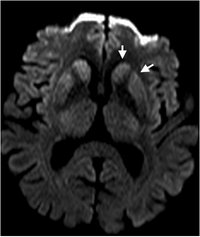

Creutzfeldt-Jakob - DWI - axial

Typische Signalsteigerung Ncl. Caudatus und Putamen.